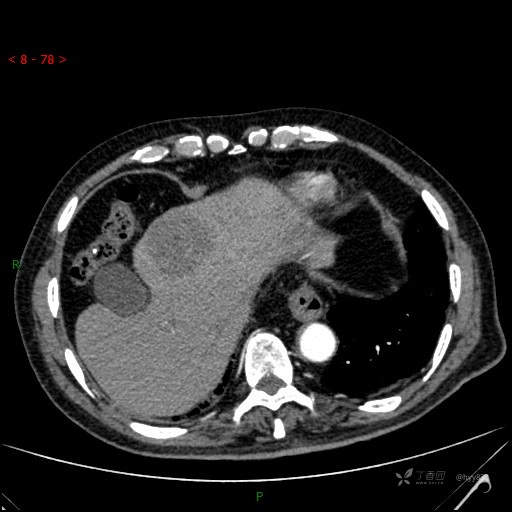

年龄:71岁

性别:男

简要病史: 间断发热、咳嗽3天,超声发现肝占位

临床诊断:肝占位

增强动脉期